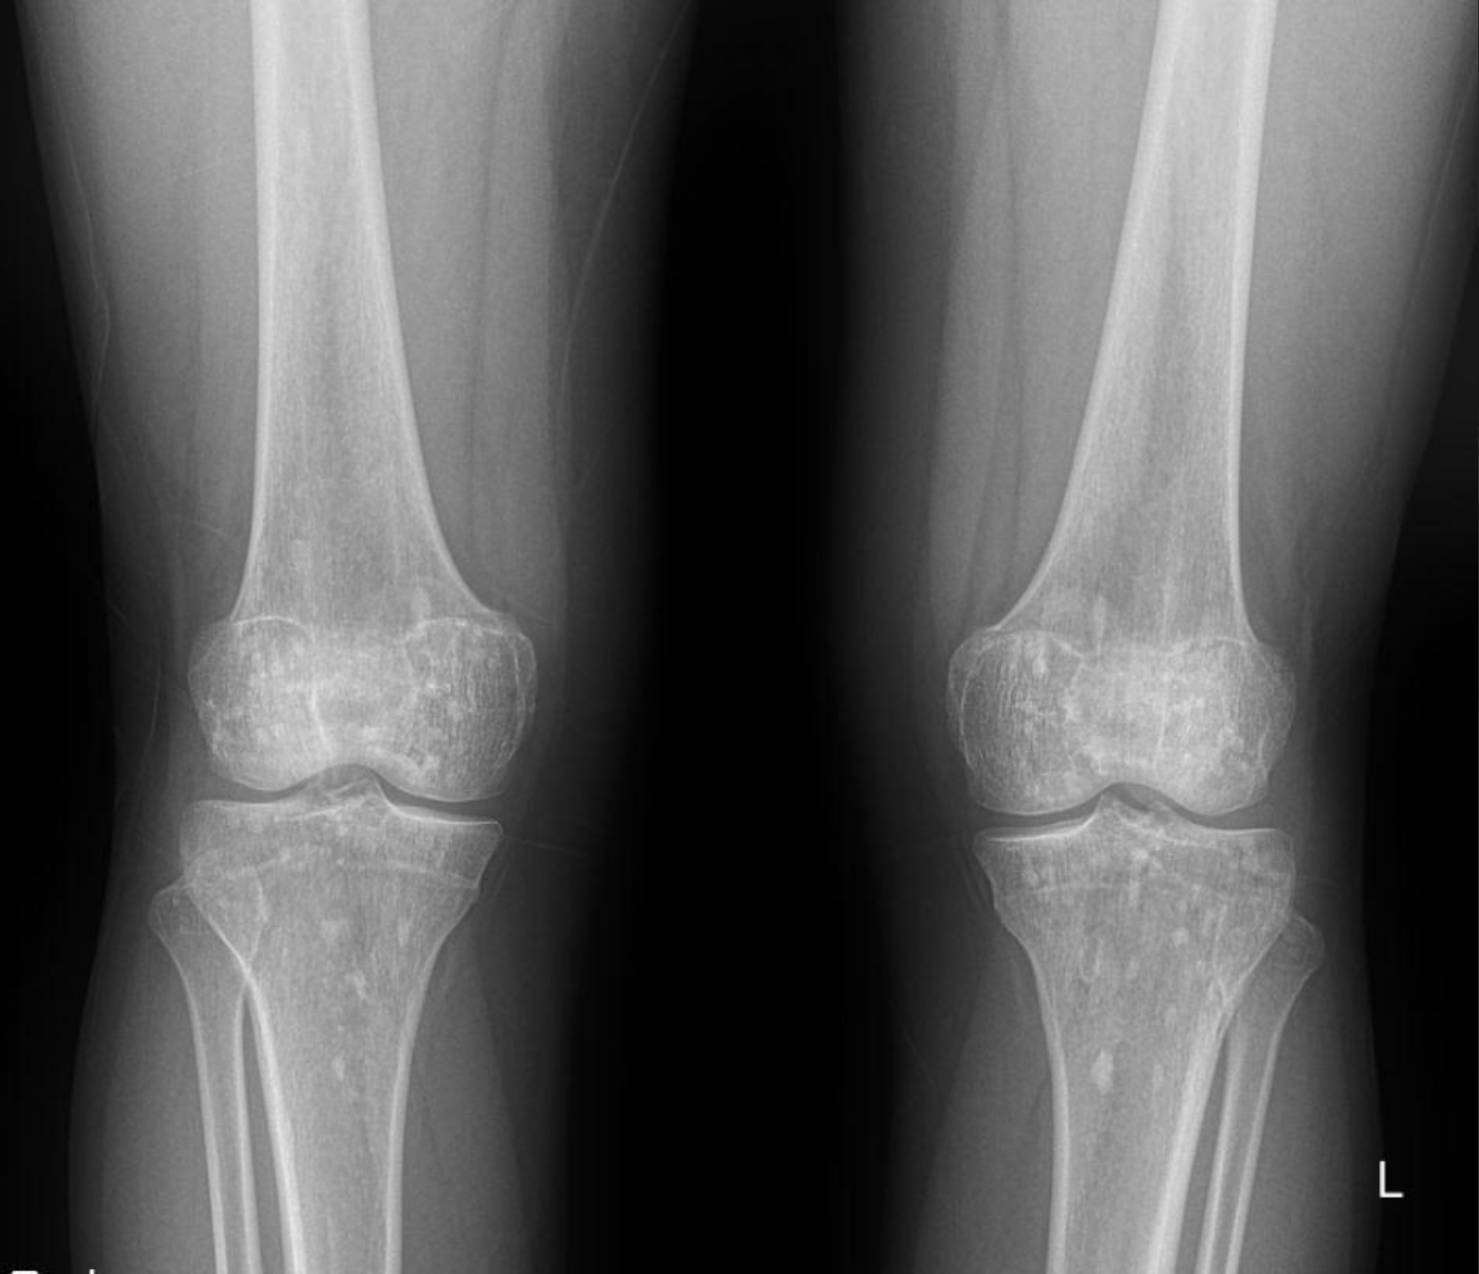

The X-rays of the pelvis, knees, elbows, wrists, and ankles demonstrate multiple, discrete, well-circumscribed sclerotic (densely opaque) lesions distributed symmetrically throughout the bones. These lesions are typically ovoid or spherical, varying in size, and are predominantly located in the epiphyses and metaphyses of long bones, as well as in the carpal and tarsal bones and the pelvic girdle.

Specifically:

- Knees: Both distal femurs and proximal tibiae show widespread small, dense sclerotic foci within the epiphyses and metaphyses. The joint spaces appear preserved.

These widespread, symmetrically distributed sclerotic bone islands are pathognomonic for hereditary osteopoikilosis (also known as osteopathia condensans disseminata). This condition is typically benign and often discovered incidentally. While not directly related to her renal artery stenosis or hypertension, its discovery is crucial for patient management as it can sometimes be associated with other connective tissue disorders, though often it is an isolated finding.